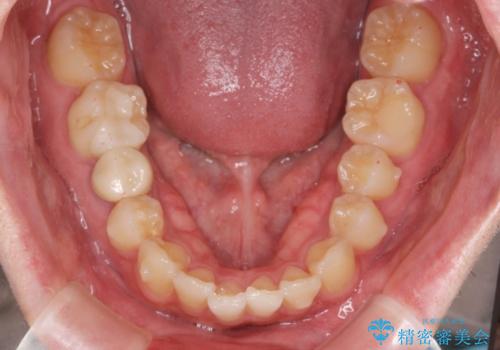

前歯のがたつきをなおしたい マウスピース矯正

- 気になる前歯のがたつきをきれいにしたい。と矯正治療を希望され来院されました。

大きな歯列の乱れはないため、倒れ込んでいる奥歯の傾きの改善、前歯のがたつきを改善する治療を計画します。

見た目が良くなっただけではなく、歯ブラシがしやすくなった!と治療後の歯並びに喜んでいただくことができました。